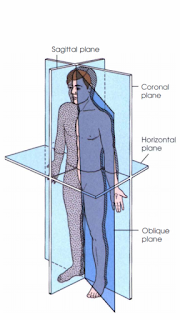

Body Plane

Dimensi itu penuh tubuh manusia dapat dilihat dari posisi anatomi. Dapat dibagi secara efektif melalui penggunaan gambaran bidang tubuh. Potongan bidang tubuh ini mengiris seluruh tubuh pada tingkat yang ditentukan dari segala arah. Berikut 4 bidang tubuh yang berdasar dalam radiografi :

1. Sagital

Sagittal plane membagi seluruh tubuh atau bagian tubuh menjadi bagian kiri dan kanan. Bidang ini membagi tubuh secara vertikal melalui depan ke belakang. Mid sagital Point adalah spesifikasi dari bidang sagital yang mana merupakan garis tengah dari tubuh dan membagi tubuh menjadi bidang bagian kiri dan bagian kanan..

2. Coronal

Coronal Plane membagi seluruh tubuh atau bagian tubuh menjadi bagian anterior dan posterior. Bidang ini membagi tubuh secara vertikal melalui Sisi satu ke Sisi Lainnya. Mid Coronal Plane adalah spesifikasi bidang sagital yang mana merupakan garis tengah dari tubuh dan membagi tubuh menjadi bagian anterior dan posterior..

3. Horizontal

Bidang ini membagi tubuh menjadi bagian Superior dan inferior atau bagian bawah. Biasanya juga disebut transverse, axial / cross sectional plane.

4. Oblique

Oblik atau bidang miring adalah bidang-bidang yang tidak sesuai dengan ketiga spesifikasi ketiga bidang sebelumnya. Bidang bidang miring dapat berlokasi di sembarang lokasi seperti yang digunakan untuk pemeriksaan hati pada MRI.

Gambar : bidang tubuh